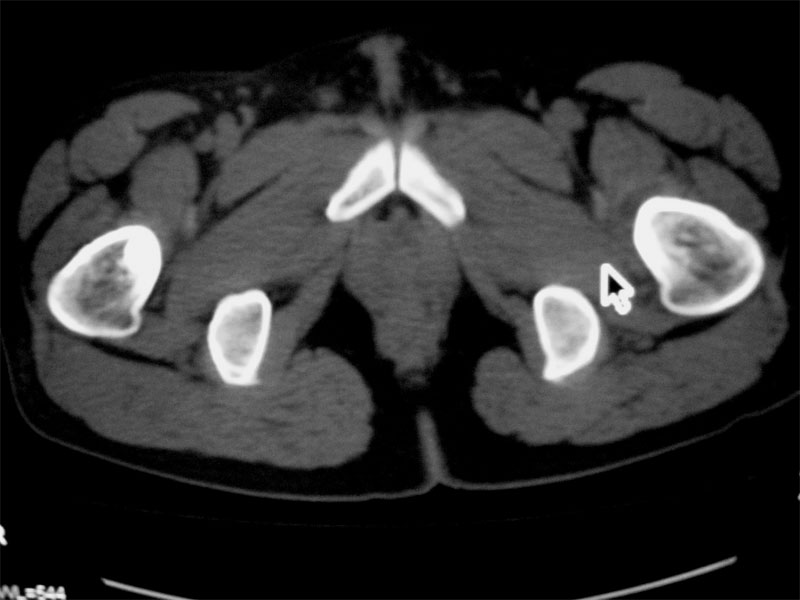

标题: CT16604:男32岁,左髋关节处疼痛月余 [打印本页]

标题: CT16604:男32岁,左髋关节处疼痛月余

左侧髋关节少量积液.上传骨窗

建议提供骨窗资料

考虑左股骨头缺血性坏死;右股骨上段良性骨肿瘤,考虑成软骨细胞瘤可能。建议上传骨窗。